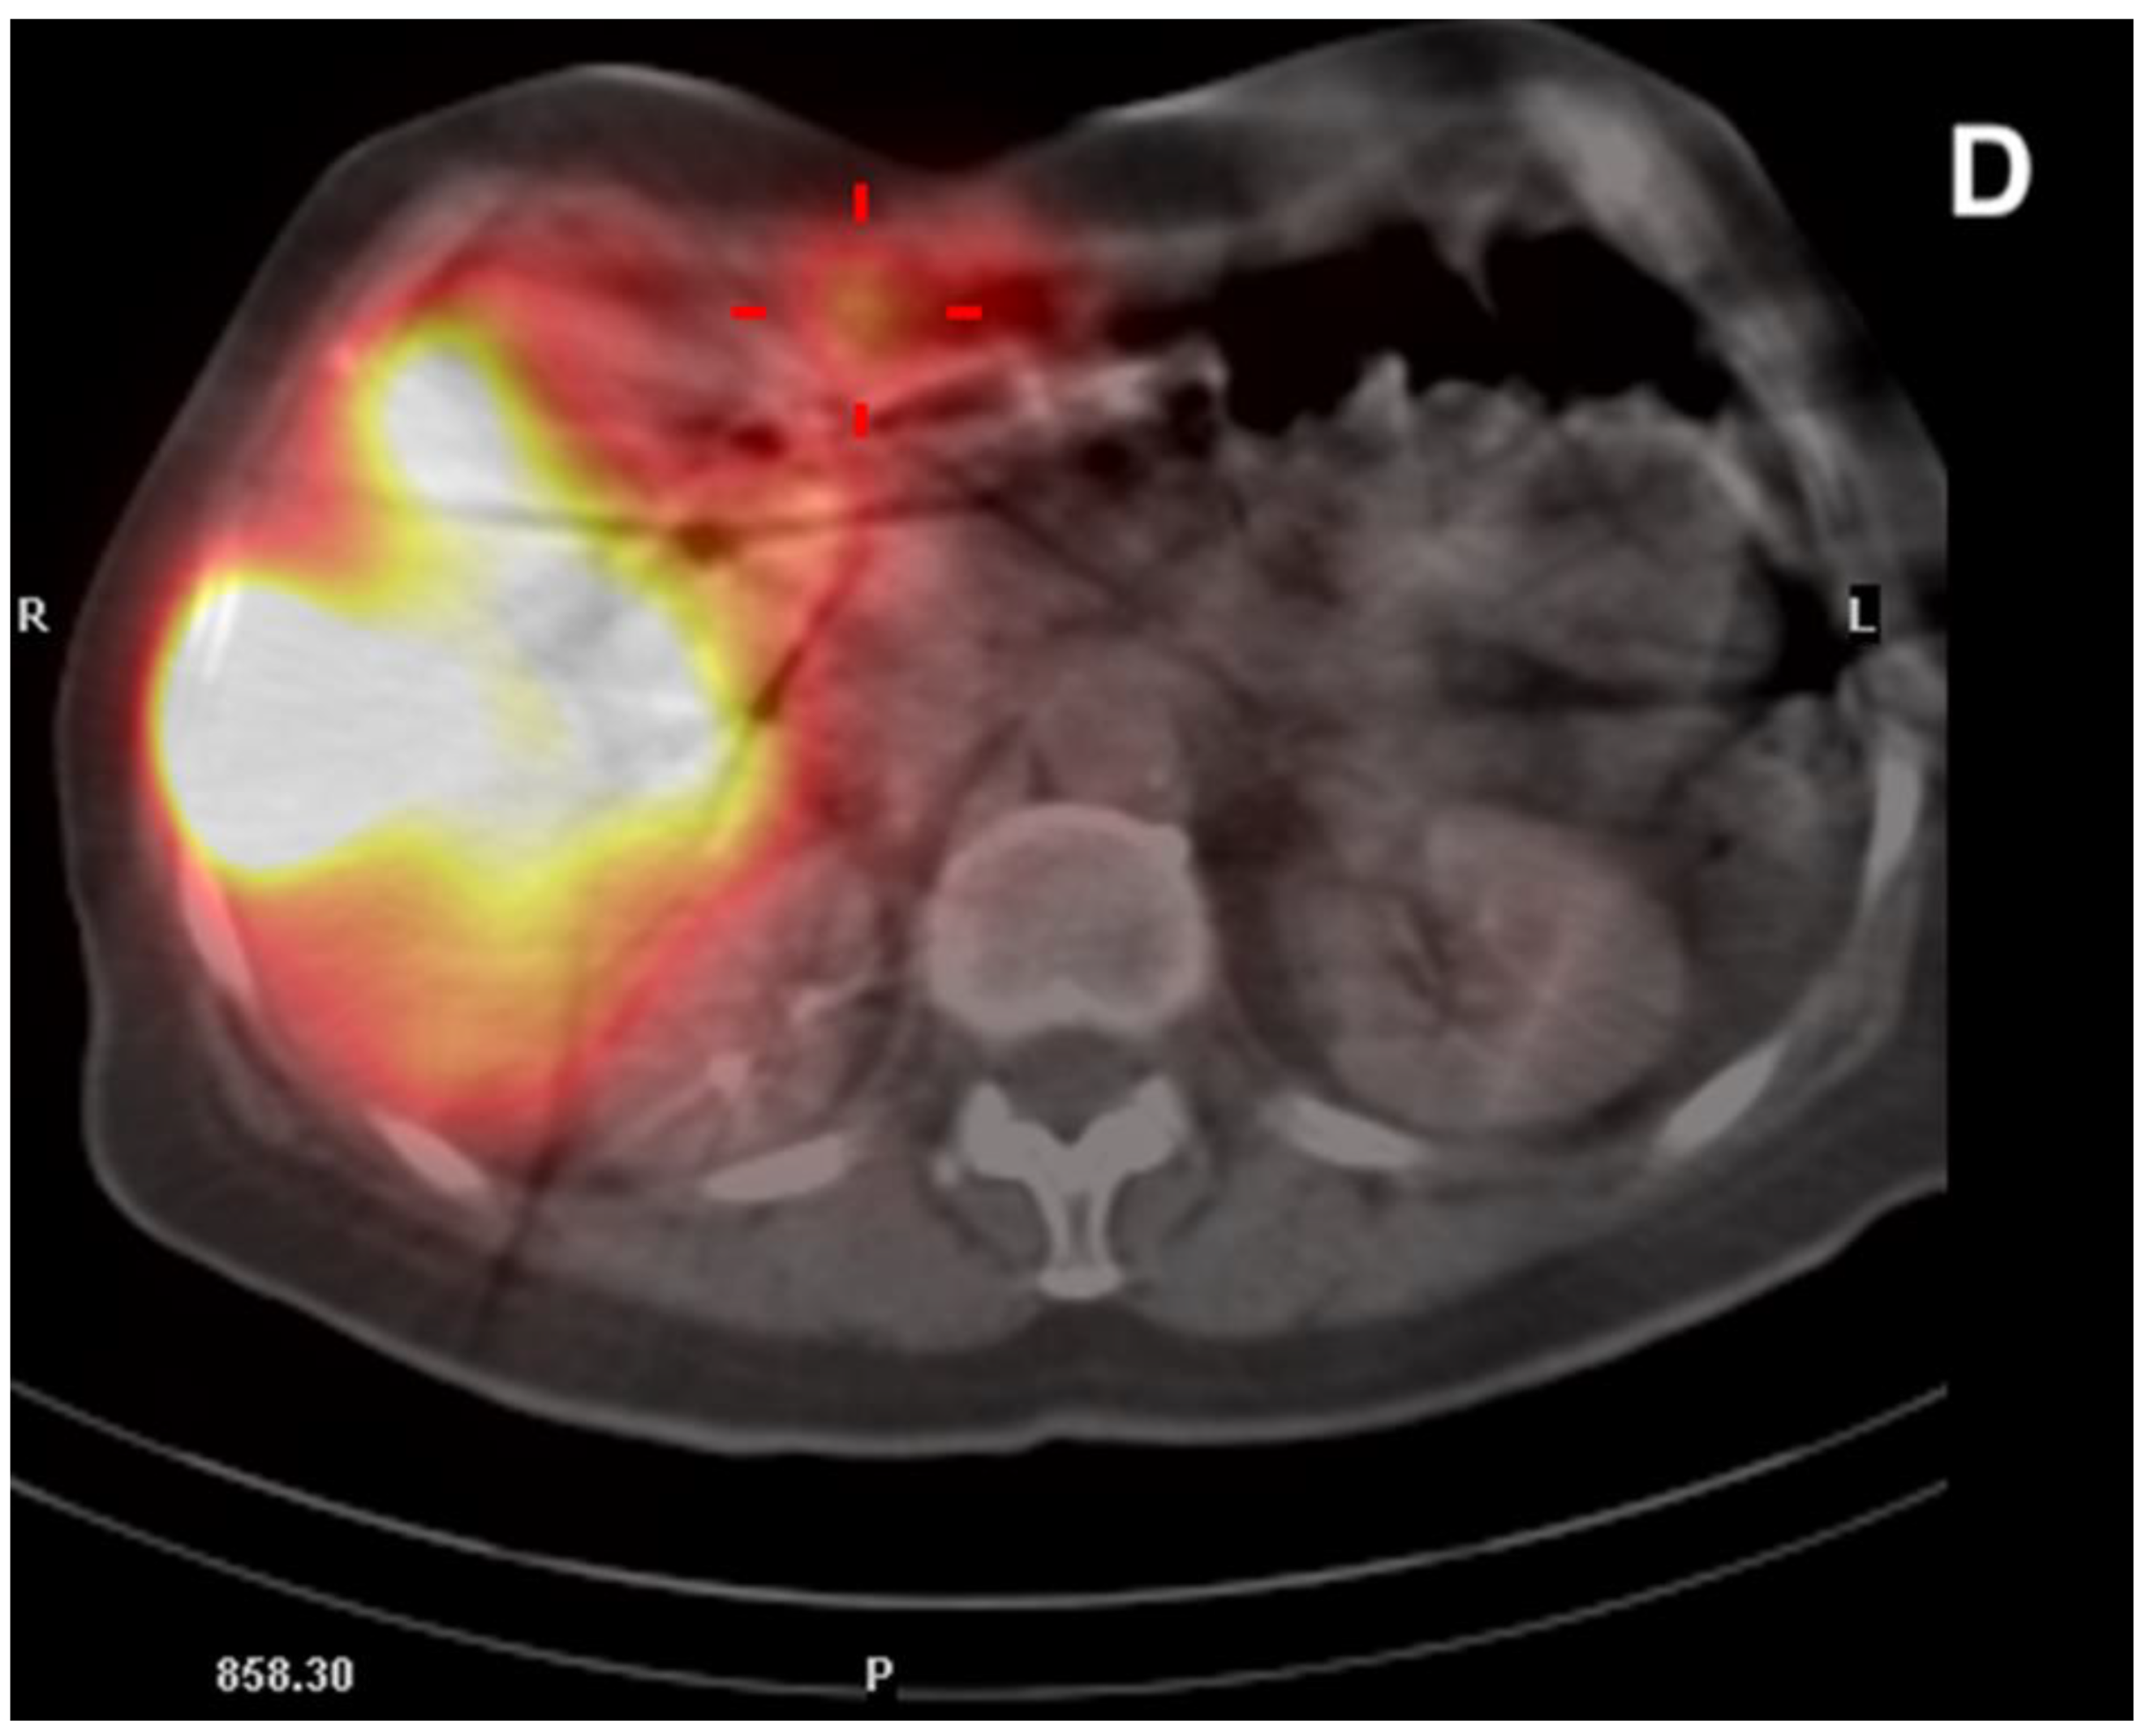

There were 20 patients after cholecystectomy. There were 30 (40%) patients with additional cystic arteries (Figure 3).

Figure 3.

Angiogram of the right hepatic artery. (A) Initially, single CA is visible (arrows) originating from the right hepatic artery division. (B) After embolization, another artery reveals multiple intrahepatic anastomoses to the gallbladder wall, and needs to be embolized. (C) There is insufficient embolization of both CA, and (D) retraction of the microcatheter reveals another CA originating proximally to the right hepatic artery division (arrows).